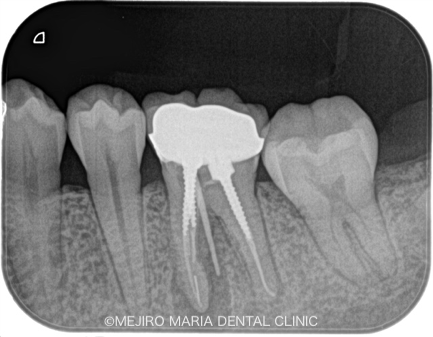

患者様は、数年前にひどい虫歯のために根管治療を受けておられましたが、数日前より左下が腫れ始め、瘻孔(フィステル/溜まった膿を排出する穴)ができたと来院されました。

レントゲンで診査すると、左下6番(第一大臼歯)の近心根(歯の根のより中心に近い部分)に根尖性歯周炎が確認でき、腫脹の原因は根尖性歯周炎であると診断しました。

また、同じ部位の根尖に、透過性の異なる充填物(赤丸)が確認できました。これは、以前の根管治療で使用していた器具が根管内で折れて、そのまま取り残されている状態です。